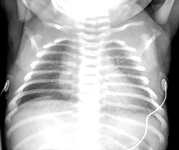

Avaliação da cianose neonatal

Hérnia diafragmática congênita

Do acervo de Ponthenkandath Sasidharan, MD; usado com permissão